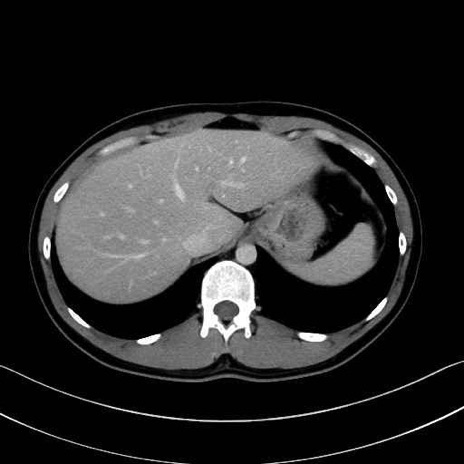

腰方形筋(quadratus lumborum muscle)のCT画像の解剖

腰方形筋 (Quadratus lumborum)